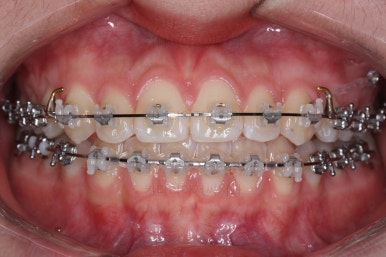

각설하고 위의 사진들은 부산치아교정잘하는곳 키다리아저씨치과에서 처음 내원하셨을 때의 사진입니다.

입매는 크게 나쁘진 않았으나 아랫입술-턱끝까지 이어지는 S라인이 너무 깊어 아랫입술이 약간 뒤집어진 형태를 보였어요.

그리고 오른쪽 위 송곳니가 덧니처럼 볼록하여 웃거나 말할 때 자신감 있게 입을 벌리지 못하고 있었어요.

아랫니는 크게 심하지 않았고 윗니 앞니쪽에 치열이 삐뚤한 것을 볼 수 있어요.

그리고 위아랫니의 중앙선도 어긋나 있는 것으로 봐서 왼쪽과 오른쪽의 교합 자체도 다르고 문제가 있음을 알 수 있었어요.

각각 왼쪽, 오른쪽의 교합의 모습입니다.

가장 좋은 교합은 위아래 치아들이 지그재그로 톱니바퀴 물리듯이 맞아들어가야 하는데 오른쪽 사진들 보면 중간중간 빈틈도 많이 보여요.

이런 교합은 장기적으로 치아 수명을 단축시킬 수 있습니다.